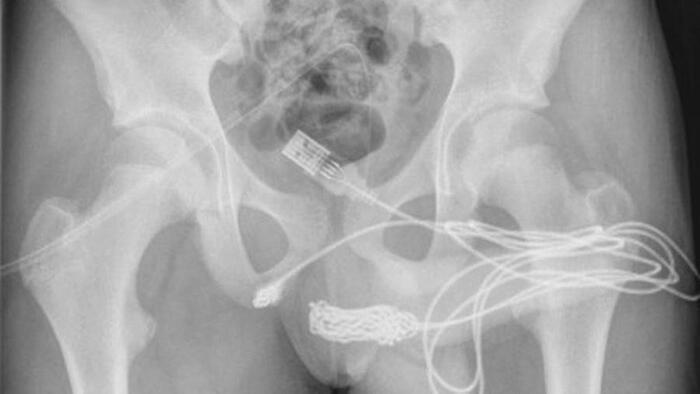

Segundo o tabloide Daily Star, do Reino Unido, o garoto foi levado ao hospital e passou por uma radiografia, que mostrou a gravidade da situação.

O cabo não apenas ficou preso na parte interna do pênis, como também fez alguns nós e ficou emaranhado na uretra.

“O paciente era um adolescente saudável e em boa forma, sem histórico de distúrbios de saúde mental. As duas pontas do fio USB estavam saindo do meato uretral externo, enquanto a parte do meio do fio permanecia dentro da uretra”, escreveram.